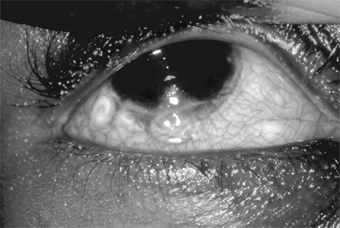

Patients with atopic dermatitis (eczema) often also have atopic keratoconjunctivitis. The symptoms and signs are a burning sensation, mucoid discharge, redness, and photophobia. The lid margins are erythematous, and the conjunctiva has a milky appearance. There are fine papillae, but giant papillae are less developed than in vernal keratoconjunctivitis and occur more frequently on the lower tarsus-unlike the giant papillae of vernal keratoconjunctivitis, which are on the upper tarsus (Figure 5-12). Severe corneal signs appear late in the disease after repeated exacerbations of the conjunctivitis. Superficial peripheral keratitis develops and is followed by vascularization. In severe cases, the entire cornea becomes hazy and vascularized, and visual acuity is reduced. The disease may be associated with keratoconus.

Figure 5-12

Figure 5-12: Moderate to marked papillary response of upper tarsus seen in atopic keratoconjunctivitis.